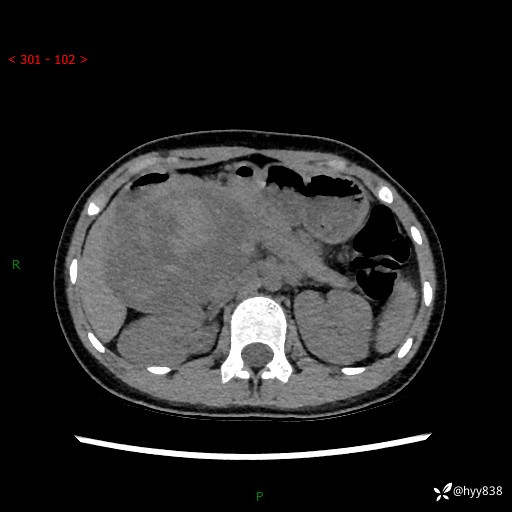

病例小姑娘,超声提示上腹部巨大包块。平扫就能轻松搞定的病变--结果公布

性别:女

年龄:13岁

简要病史:超声提示上腹部巨大包块

上腹部CT平扫

胰腺实性假乳头状瘤 (17)